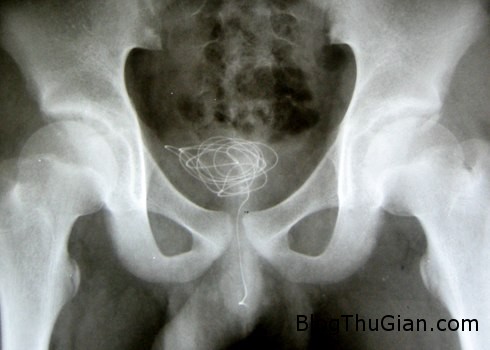

Sợi dây điện nằm trong bàng quang của bệnh nhân. Ảnh: Bác sĩ Phạm Ngọc Thạch

Tại Bệnh viện Nhi Đồng 2, qua chẩn đoán hình ảnh, các bác sĩ xác định một đầu sợi dây điện lơ lửng ngoài niệu đạo, phần còn lại nằm trọn trong bàng quang. Do vị trí và tình trạng dị vật không phức tạp, các bác sĩ đã đưa dị vật ra ngoài từ lỗ tiểu mà không cần mổ hở. Ngoài ra, có thuận lợi nữa là dây điện chưa bị rối.